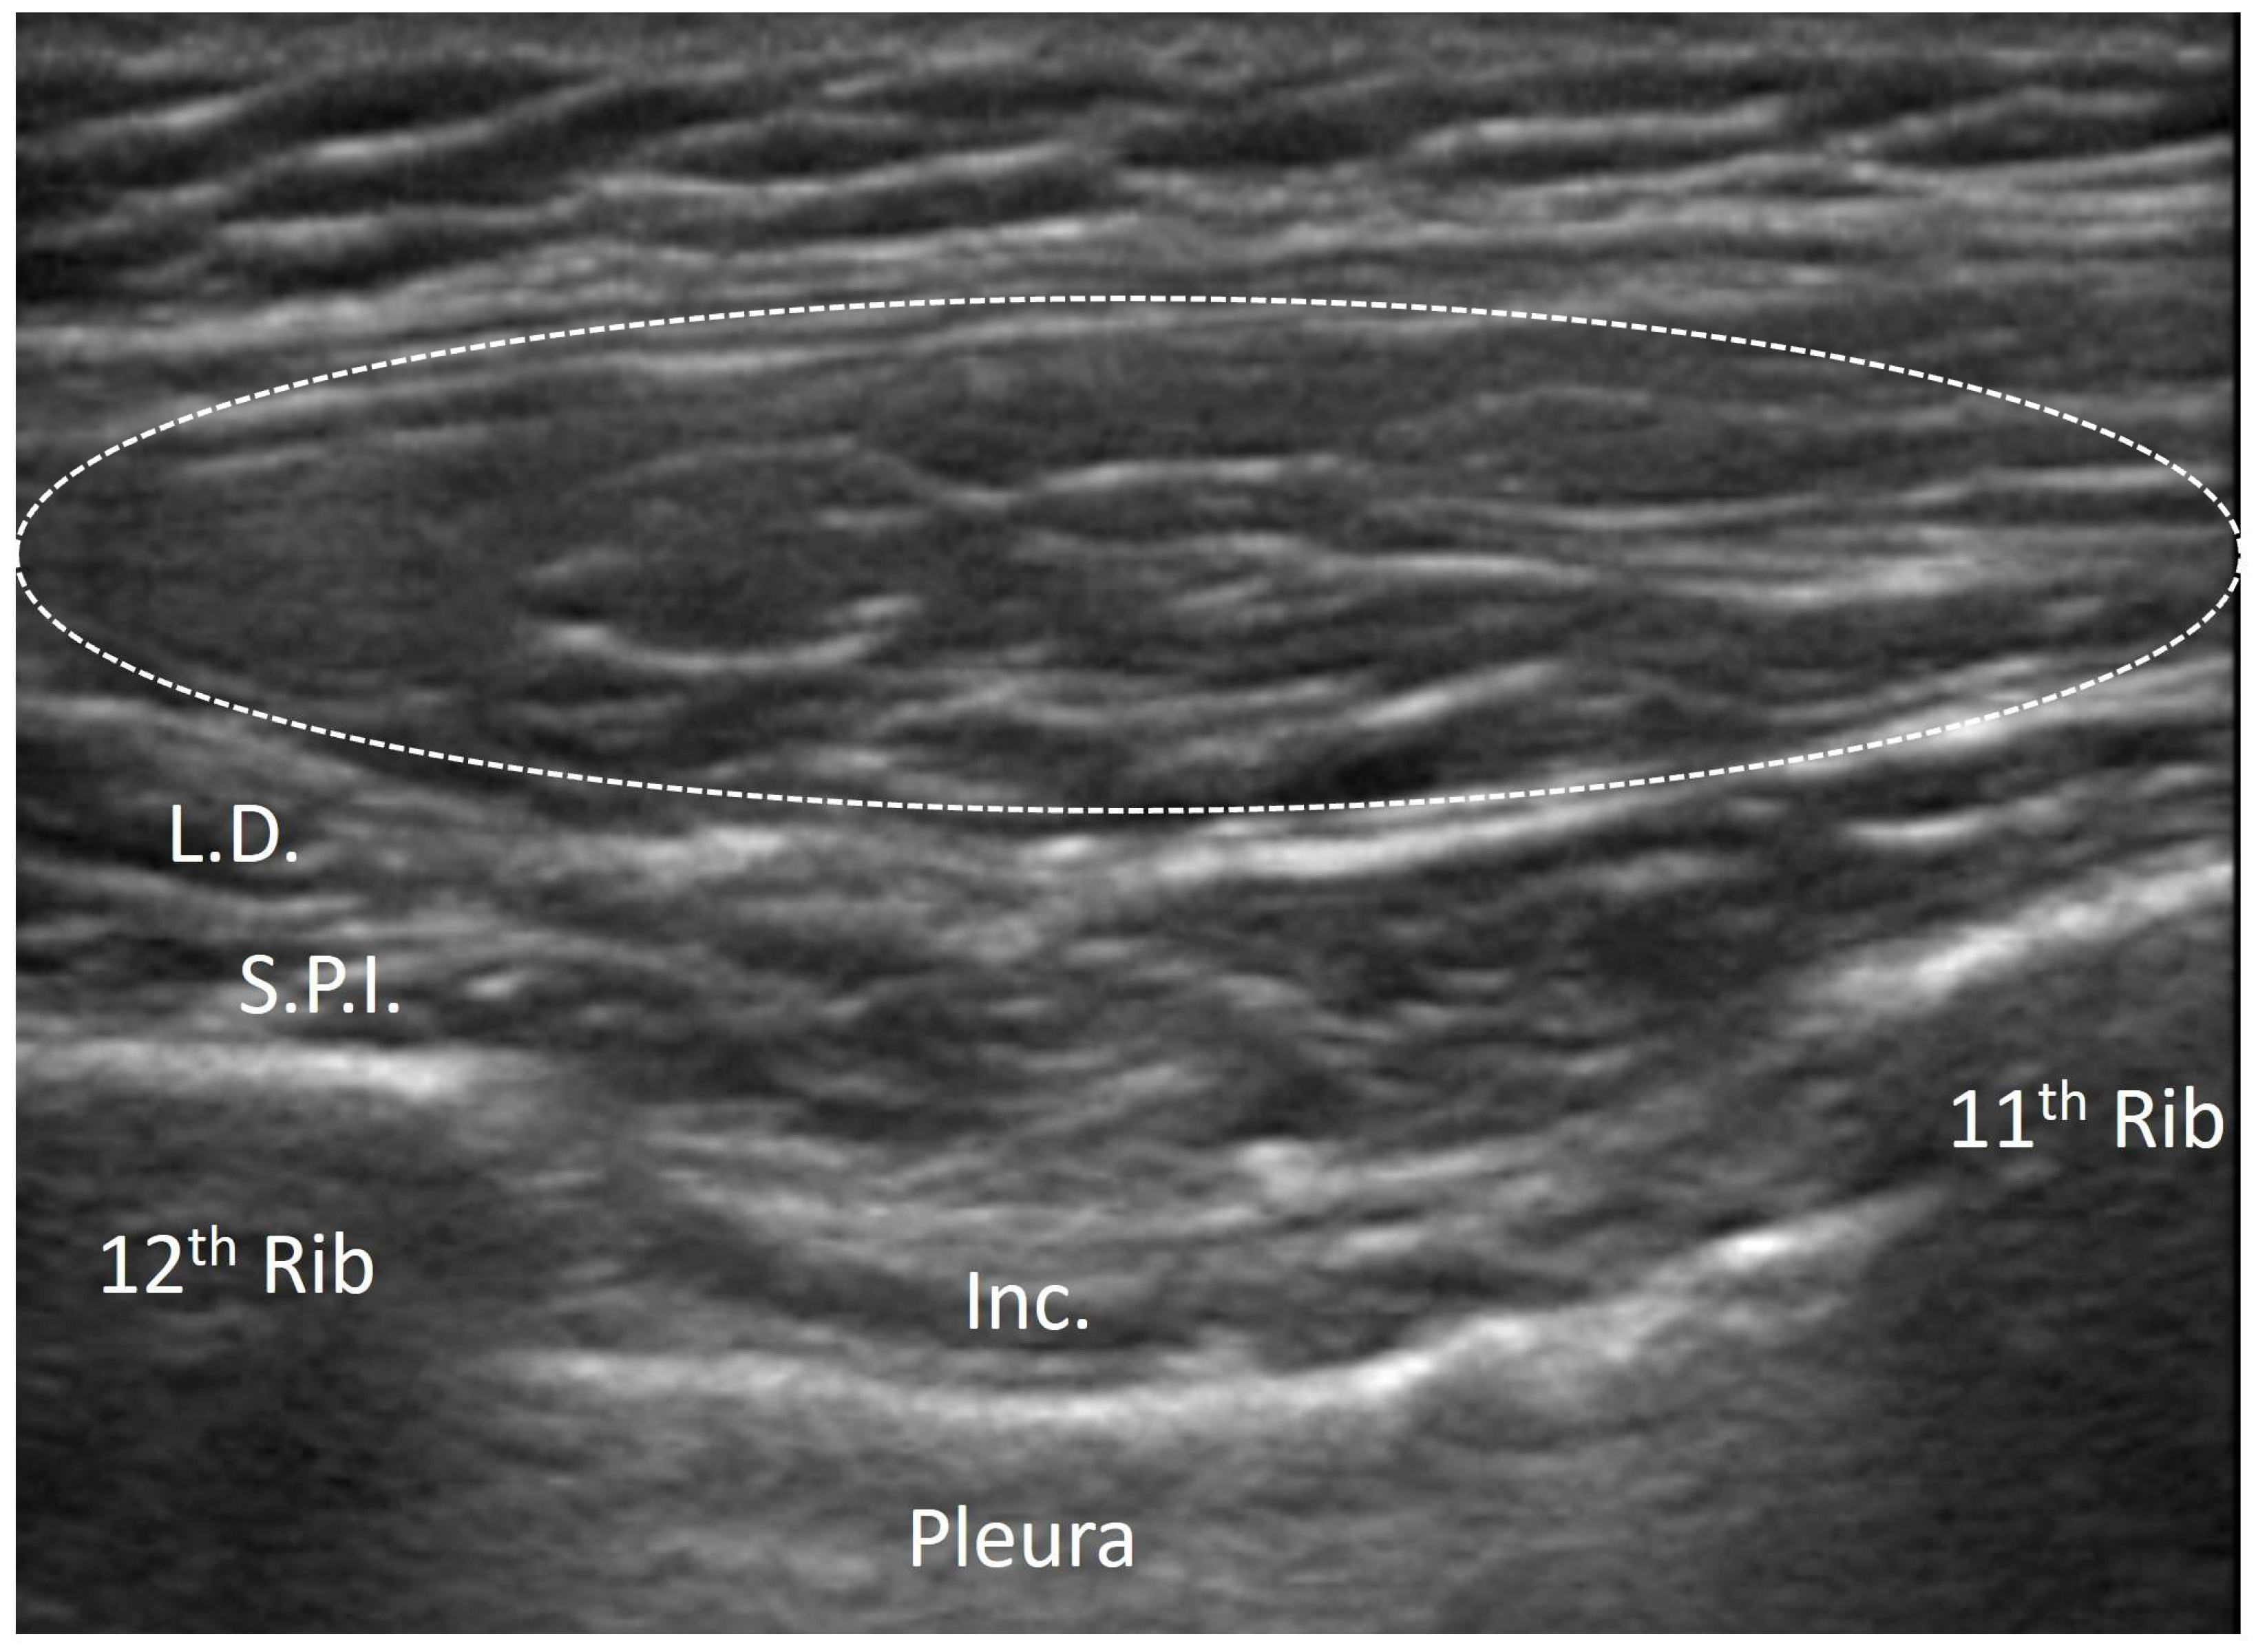

3.1. Normal Ultrasonographic Appearance of Fasciae

- Pirri, C.; Pirri, N.; Guidolin, D.; Macchi, V.; Porzionato, A.; De Caro, R.; Stecco, C. Ultrasound Imaging of Thoracolumbar Fascia Thickness: Chronic Non-Specific Lower Back Pain versus Healthy Subjects; A Sign of a “Frozen Back”? Diagnostics 2023, 13, 1436. [Google Scholar] [CrossRef] [PubMed] [PubMed Central]